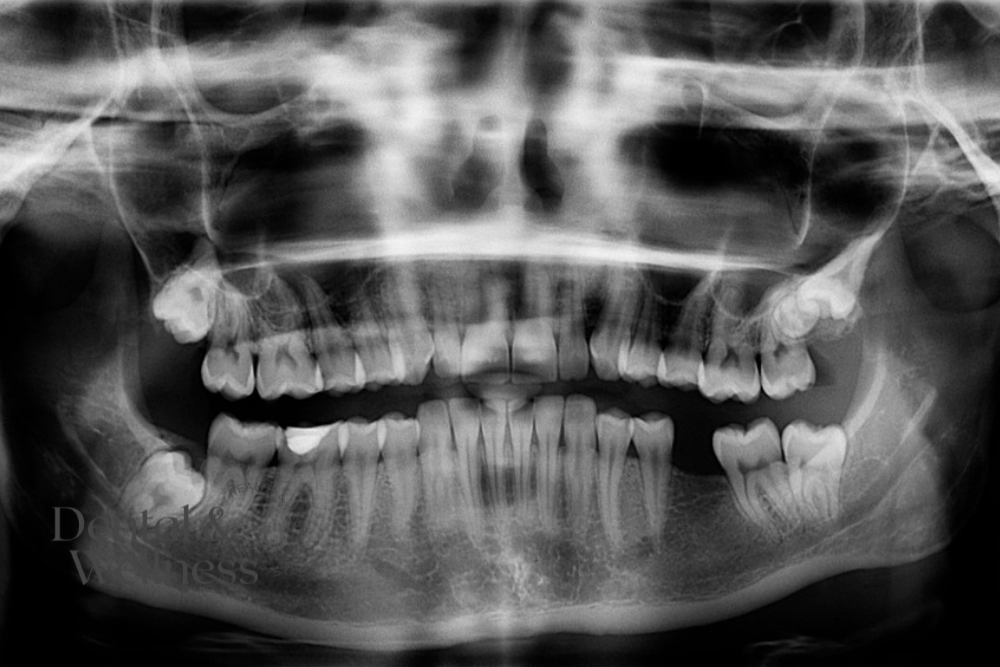

The process starts with a clinical exam and radiographs (usually X-rays or OPG scans). These help dentists evaluate the tooth’s position, level of impaction, and closeness to nerves or sinuses.